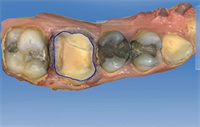

Dentaltown Learning Online- The Aesthetic Full Mouth Rehabilitation by Dr. John Nosti

Dentaltown Learning Online is proud to present John Nosti's latest extraordinary CE course...."The Aesthetic Full Mouth Rehabilitation" This course can be found here... Full Mouth Rehabilitations are one of the most difficult types of cases to handle in practice today. Many times these patients...  Read More